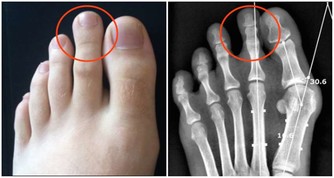

四種表現暗示白血病到來,不可當成小病一直“拖”

兩個多月前喬女士的孩子突然發高燒,對於一個二胎媽媽來說,她對孩子發燒一事已經很有經驗,無非就是前期物理降溫,若是溫度繼續升高那就吃退燒藥。她覺得孩子生病是成長必經之路,沒啥好稀奇的,就這樣斷斷續續吃藥、輸液,拖了兩個多月。

後來孩子說自己關節疼,喬女士認為生病了難免會覺得不舒服,自己感冒時也會覺得腰酸背痛的,於是安慰孩子沒關係,很快就會好的。直到她發現孩子身上莫名出現瘀青,牙齦還總是流血,她才意識到有點不正常。拿到報告單後她崩潰大哭,覺得是自己害了孩子,要不是自以為是拖這麼久,說不定孩子早就接受治療了。

醫生提醒:孩子貧血沒有精神、頻繁發燒降不下來、鼻腔牙齦莫名出血、關節疼痛水腫,這些都可能暗示白血病到來,若是經過用藥還沒有緩解,就不要再拖下去了,盡快就醫檢查。